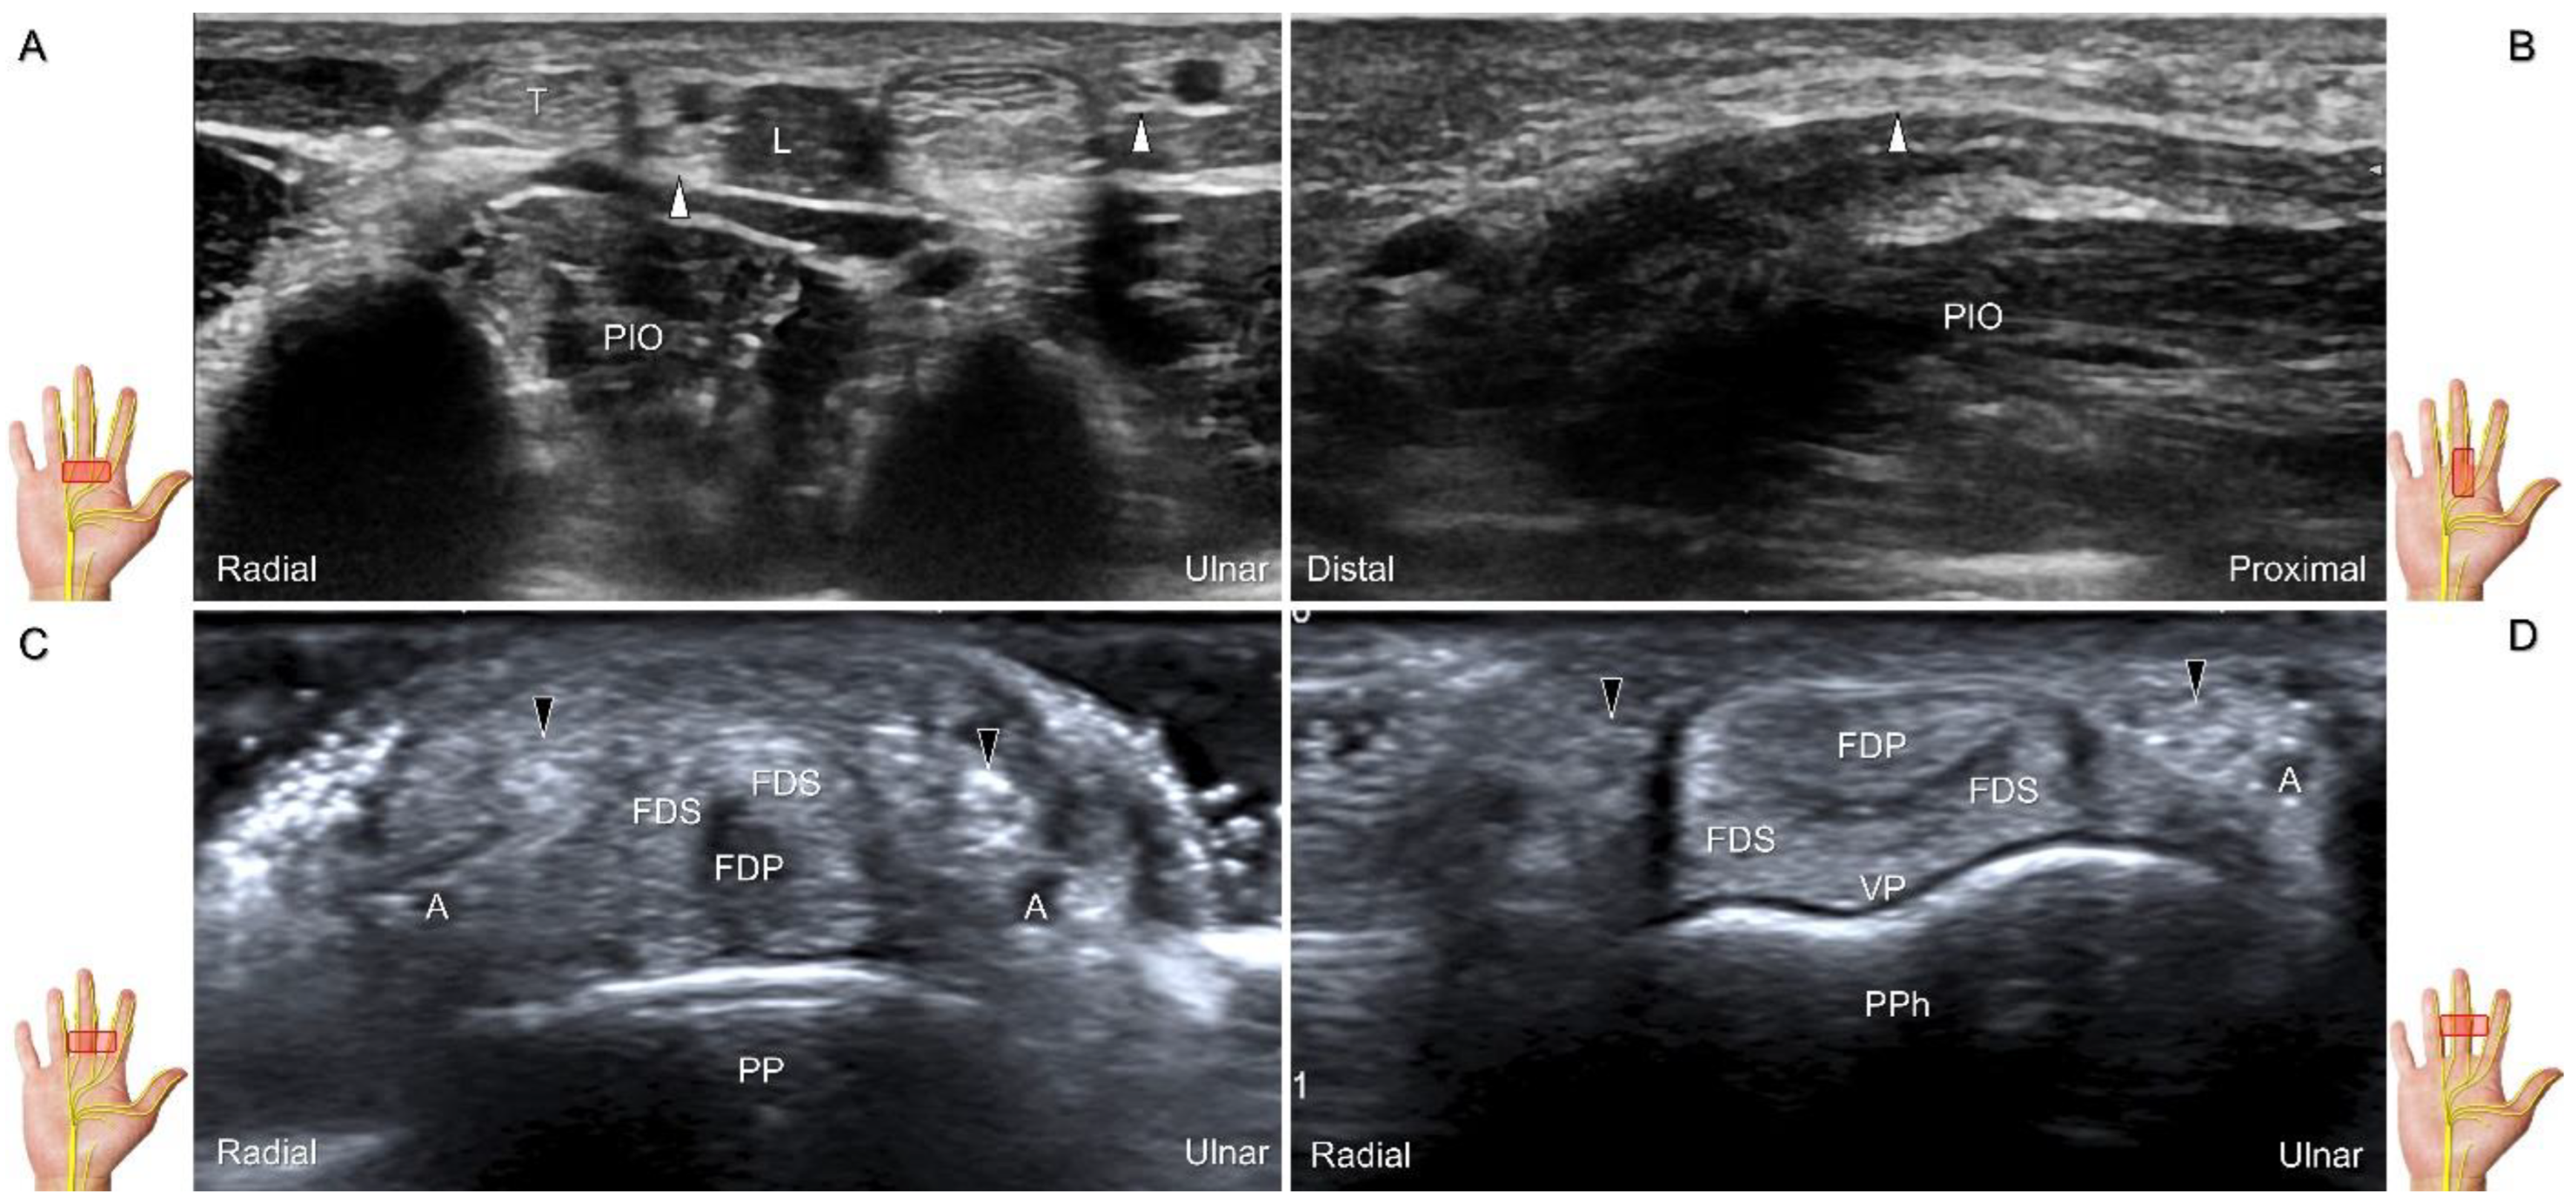

Scanning Technique

The transducer is placed on the mid-palm in the axial plane (Figure 28A). The palmar common digital nerves course beside the flexor digitorum profundus/superficialis tendons with the palmar common digital artery, and they are superficial to the palmar interosseous muscles (Figure 28B). Moving the transducer more distally, the palmar proper digital nerves can be identified alongside all phalanges (Figure 28C,D).

Figure 28. Sonographic imaging of the palmar common digital nerves in short-axis (A) and long-axis (B) views. Palmar proper digital nerves from the base (C) to the head of the proximal phalanx (D). White arrowheads: palmar common digital nerves; black arrowheads: palmar proper digital nerves. T: flexor tendon; L: lumbricalis muscle; PIO: palmar interosseous muscle; FDS: flexor digitorum superficialis tendon; FDP: flexor digitorum profundus tendon; A: artery; VP: volar plate; PP: proximal phalanx; PPh: head of the proximal phalanx.